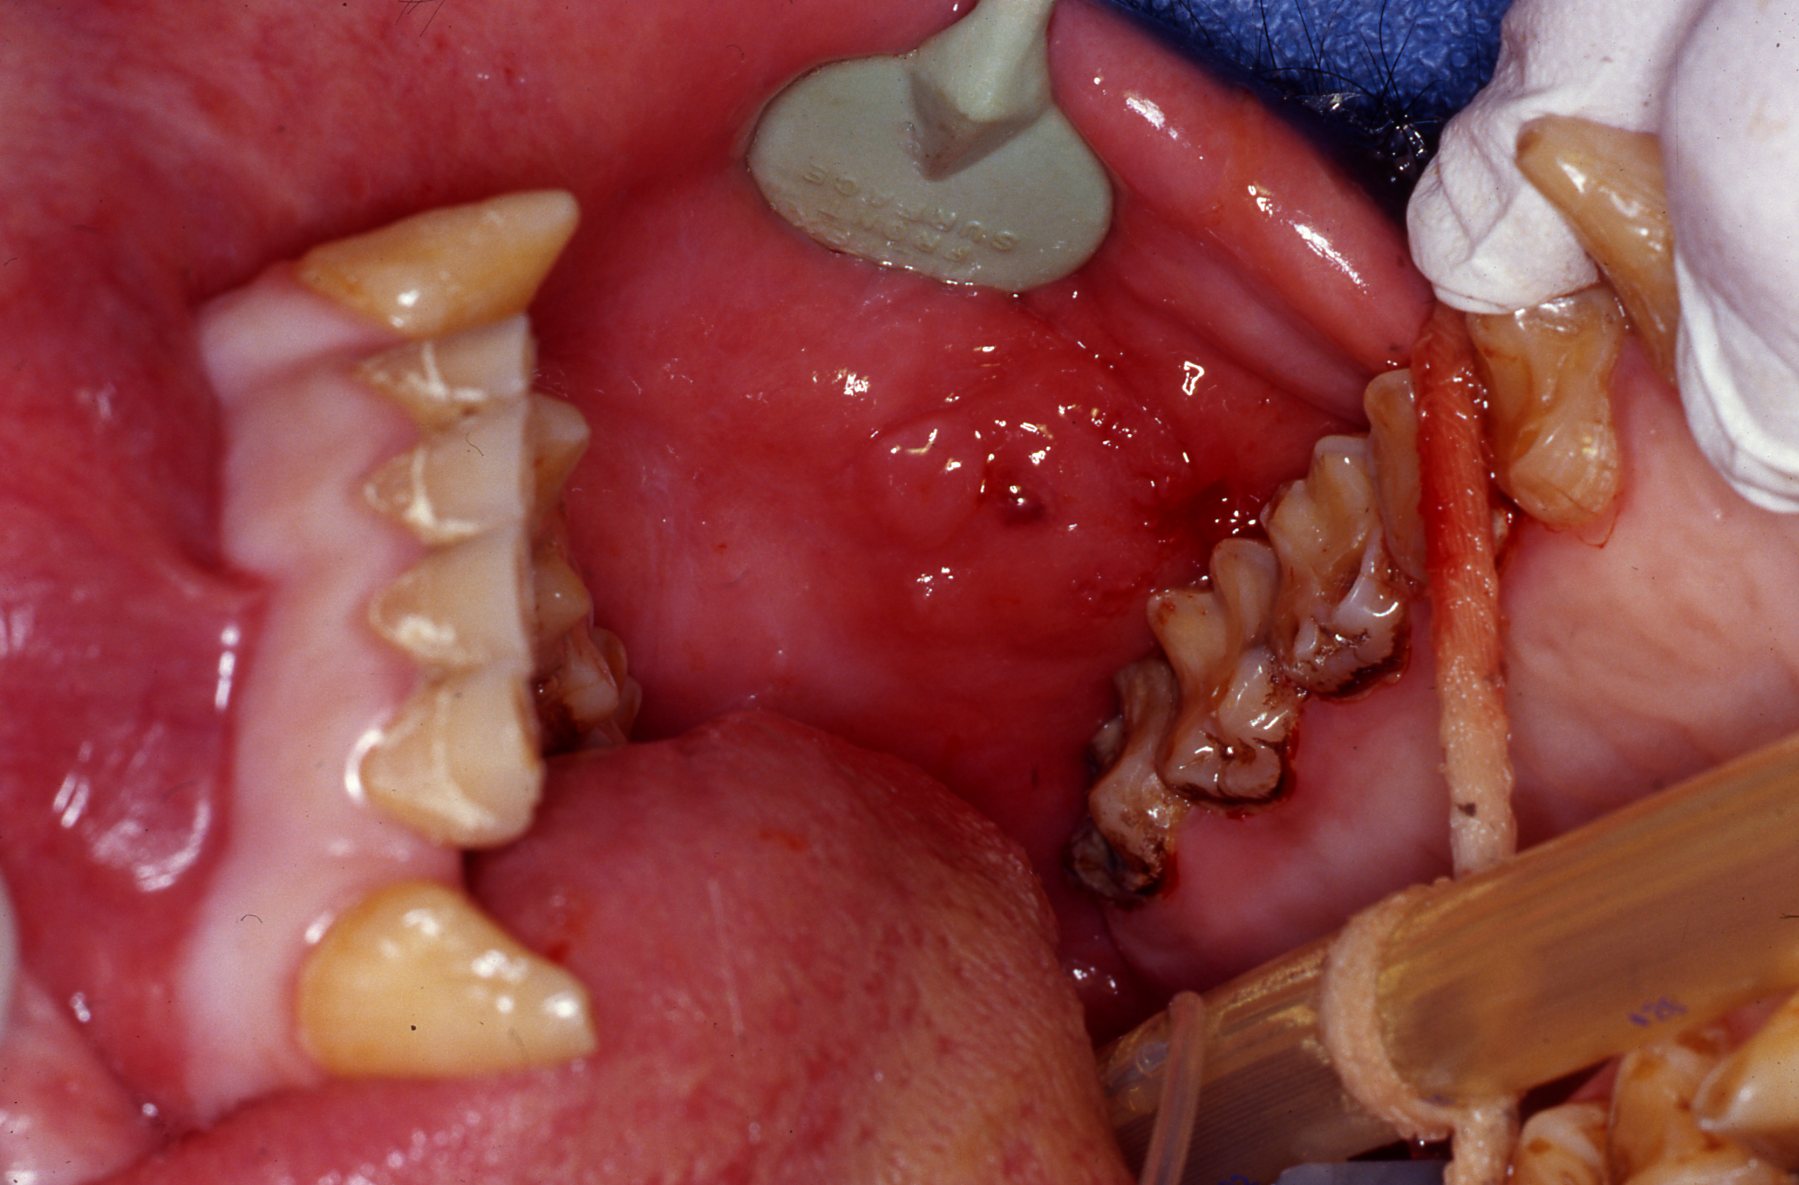

Maxillary left central incisor and lateral incisor residual roots. Region was inflamed, edematous prior to two weeks of antibiotic therapy.

Conventional dental film in position. Digital Phos Phor plates were also exposed.

Dr. Hausmann and Dr. Scheels positioning Nomad radiography unit.

Digital image reveals periapical lesion on central incisor residual root.

Incision on crest of ridge.

Luxator technique utilized to remove residual roots.

556 surgical bur used to remove approximately 2mm. of alveolar bone surrounding each root ("ditching".)

Alveoli after roots extracted

Extracted roots

Simple interrupted sutures placed with knots inside the wound so that Makanza will find it difficult to disturb them with his fingers and tongue.